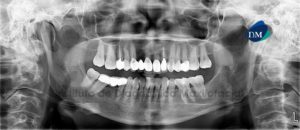

Paciente femenino, 53 años de edad, es referido al Instituto de Diagnóstico Maxilofacial (IDM) para evaluación tomográfica de los rebordes edéntulos con fines de colocar